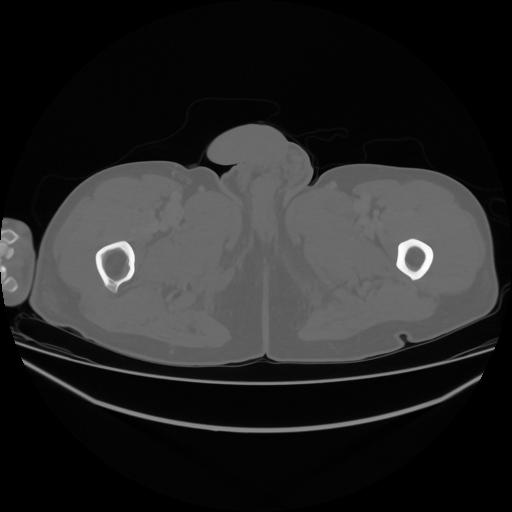

5 CUERPO,CE,Vol,1.0,CUERPO,,